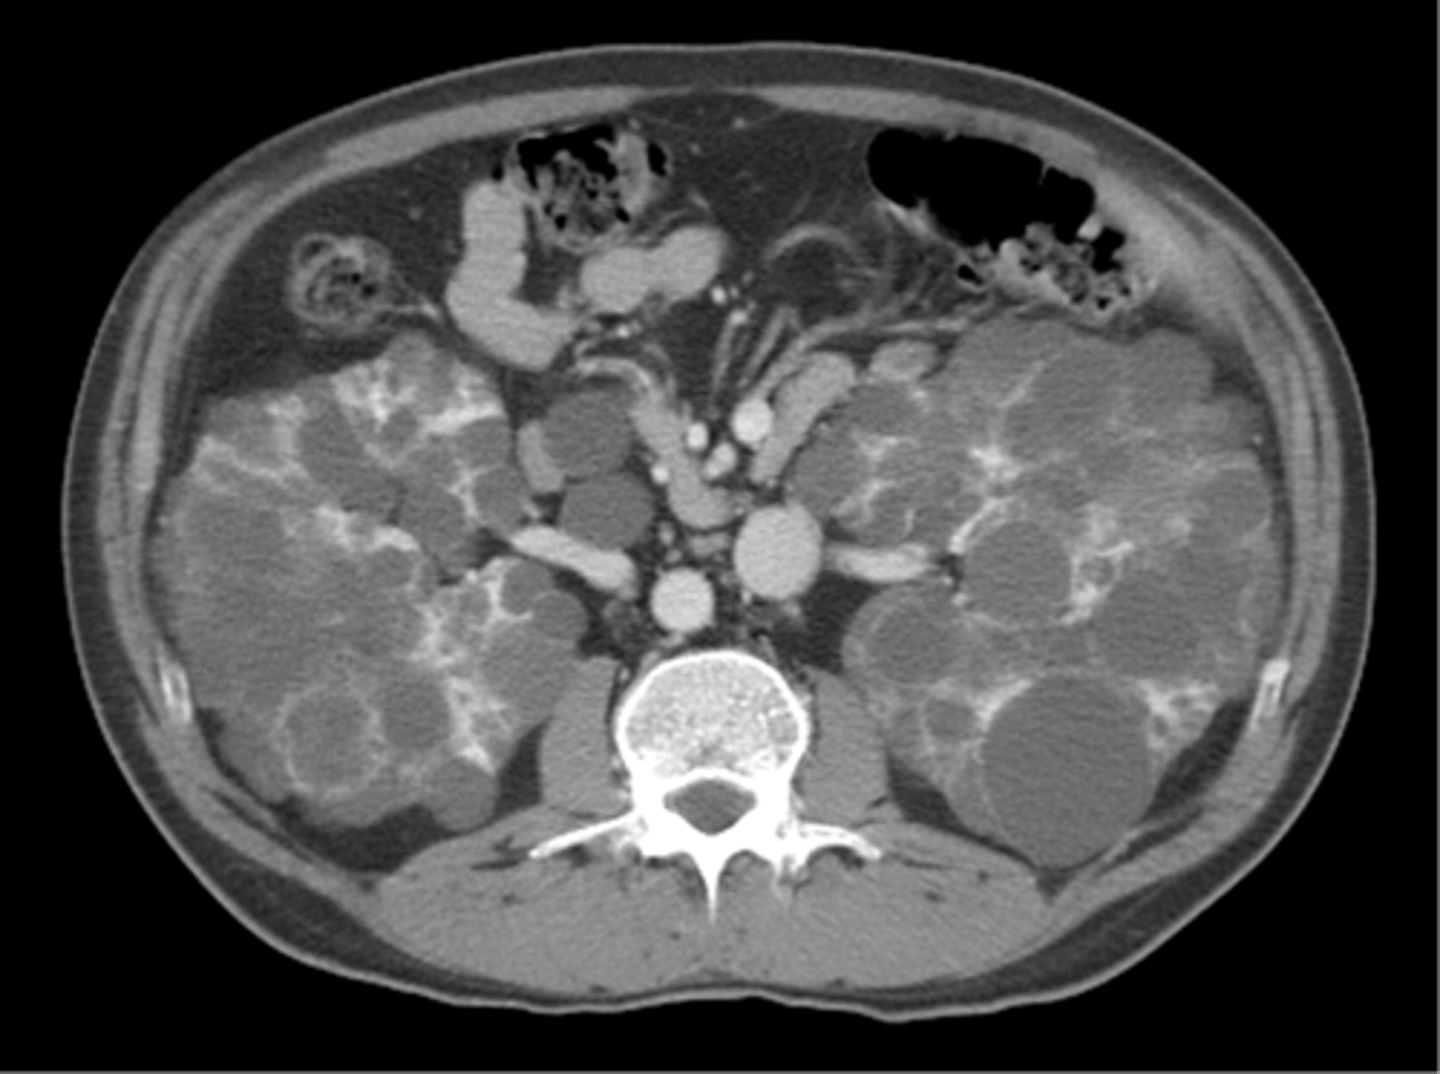

AD polycystic kidney disease

What disorder:

-85% of families have abnormality on chromosome 16 (PKD1 locus)

-remaining pts have abnormalities on chromosome 4 (PKD2 locus) --> less severe and often seen in late presenting

-Dx = imaging + Hx

-numerous cysts in cortex and medulla causing BL enlarged kidneys ultimately destroy kidney parenchyma

-Presentation = combo of flank pain, hematuria, HTN, urinary infection, calculi, progressive renal failure

autosomal dominant polycystic kidney disease

ID